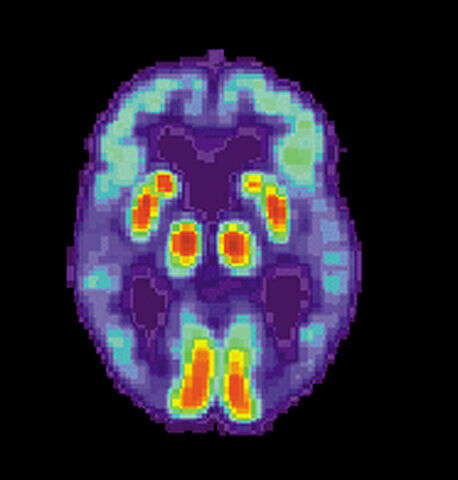

Początkowo choroba Alzheimera ma przebieg bezobjawowy, a współczesna medycyna nie zna metod pozwalających na wczesną diagnostykę. Prawdopodobnie zmiany w mózgu zachodzą już na 10 lat przed formowaniem blaszek amyloidowych lub białek tau. Kiedy pojawiają się pierwsze wykrywalne symptomy choroby, degeneracja komórek nerwowych może wynosić już 30-40%.

Rozpoznanie choroby Alzheimera polega na określeniu u pacjenta typowych cech otępienia. Stuprocentowa diagnoza wymaga występowania silnych i typowych objawów. Każde problemy z pamięcią powinny zapalić u nas lampkę alarmową i wymusić wizytę u lekarza. Ci przeprowadzają różnego rodzaju testy do rozpoznaniu choroby Alzheimera, m.in. test zegara czy ocenę stanu psychicznego.